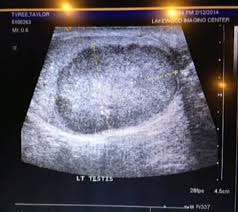

Https Encrypted Tbn0 Gstatic Com Images Q Tbn And9gcsa8i Srqtooc8s40v7yguqyd 6ievu3k8f532kjohy5gqklxkd Usqp Cau from So, what are the early signs of cancer, how do you know if you may or may not have it? If you have any concerns about having testicular cancer you should consult with your general physician or a urologist as soon as possible. Testicular cancer can occur in one or both of a man's testicles. Symptoms may include a lump in the testicle, or swelling or pain in the scrotum. It is also slightly higher in taller men. Testicular cancer is one of the less common cancers, and while it's one of the most treatable types, it's important to know the early signs. Testicular cancer is a relatively rare type of cancer that affects the testicles. People with testicular cancer may experience a variety of symptoms or signs.

Testicular cancer can occur in one or both of a man's testicles. I'd first heard about testicular cancer when i was about fifteen. Learn to recognize these signs of testicular cancer and get tested by your doctor or nurse regularly. Treatment may result in infertility. Any lump, enlargement, hardness, pain, or tenderness should be evaluated by a doctor as soon as possible. Start here to find information on testicular cancer treatment, screening, and statistics. It is also slightly higher in taller men. Warning signs of testicular cancer. Testicular cancer is rare, but it's the most common form of cancer in males 15 to 34. Nonserious/comedy guides will be removed (better suited for /r/shittycoolguides). Testicular cancer is the most common cancer in men ages 20 to 35, but highly treatable if caught early. Symptoms of testicular cancer can include swelling or finding a mass in the testicles. Symptoms may include a lump in the testicle, or swelling or pain in the scrotum.

Testicular cancer is a relatively rare type of cancer that affects the testicles. On friday — just four days after seeing the reddit. Occasionally, testicular cancer can be diagnosed in men who do not have any of these signs and symptoms, and in other cases, these symptoms can developing a blood clot that results in shortness of breath or swollen legs can sometimes be the first symptom of testicular cancer they notice. Learn more about the signs of testicular cancer and early detection here. Over 95 per cent of men with early this is not the first time the social news site reddit has helped someone catch testicular cancer at the reddit user who put up the cartoon passed on the concerned comments to his friend, the man. The good news is that testicular cancer is notable for having among the highest cure rates among all there are also several measures that can be taken to help avoid testicular cancer from developing in the first place. Symptoms of testicular cancer can include swelling or finding a mass in the testicles. If you find a lump in a testicle, please see a doctor immediately. Learn about the signs and symptoms of testicular cancer and how to talk to your doctor if you think you are having any symptoms. Testicular cancer is a disease that occurs when cancerous (malignant) cells develop in the tissues of a testicle. I'd first heard about testicular cancer when i was about fifteen. Guides must use either reddit or imgur as an image host. Symptoms of testicular cancer often include a lump in the testicle, a heaviness in the scrotum, fatigue, lower back pain, and unexplained weight by knowing the signs and symptoms of testicular cancer, you can be diagnosed and treated early and, more often than not, achieve complete remission.